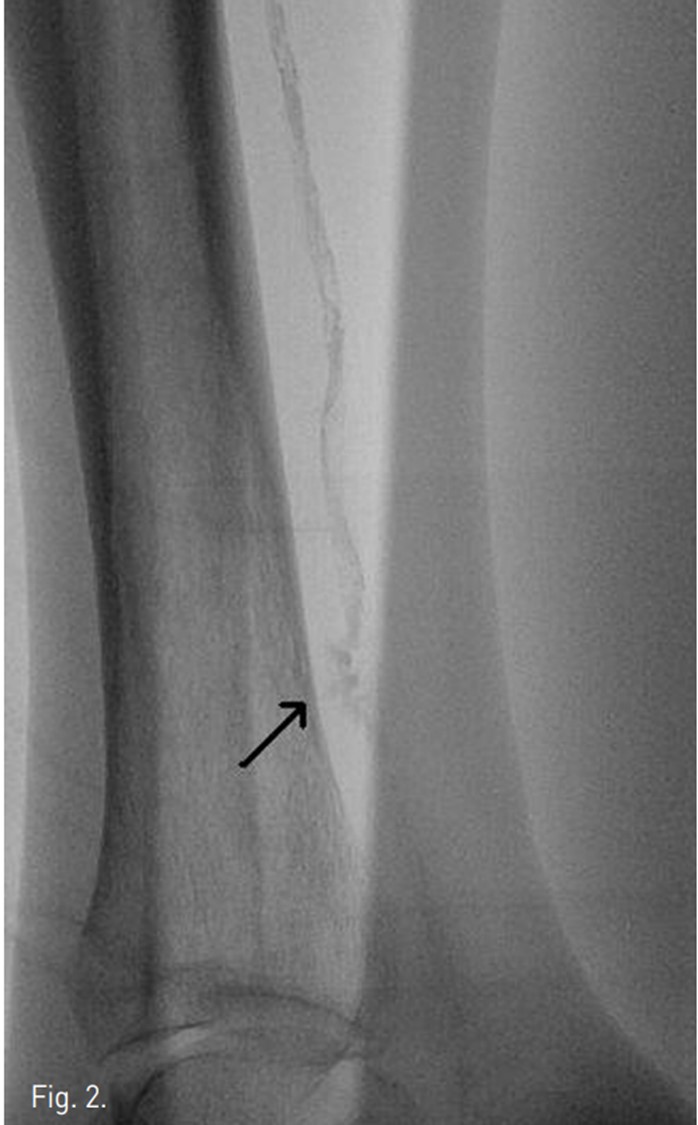

우총대퇴동맥을 antegrade puncture하여 6Fr sheath 를 삽입하였다. 4Fr Berenstein catheter(Glide catheter, Terumo, Japan)를 사용하여 우측superficial femoral artery의 협착 부분과 popliteal artery의 협착 부분을 확인하였다. 4 Fr catheter 와 J-tip guide wire (RADIFOCUS, Terumo, Japan) 로 TP trunk 끝부분의 후경골동맥 시작부위 폐색부분에서 subintimal channel내로 들어간 다음, 후경골동맥의 원위부까지 subintimal channel을 따라 J-tip guide wire를 전진 시켰으나,후경골동맥의 원위부 1/3지점에 위치하는 heavy calcification으로 인해 더 이상 wire가 원위부 후경골동맥의 true lumen까지 전진이 불가능하였다. Wire를 subintimal channel에서 조작하는 동안 heavy calcification부위에서 subintimal space가 perforation되어 wire passage를 일단 중지하였다 (Fig. 2).

Fig. 2.

Fig. 2. A posterior tibial arteriography shows perforation of subintimal space. Faint extravasation of contrast media is noted (arrow)